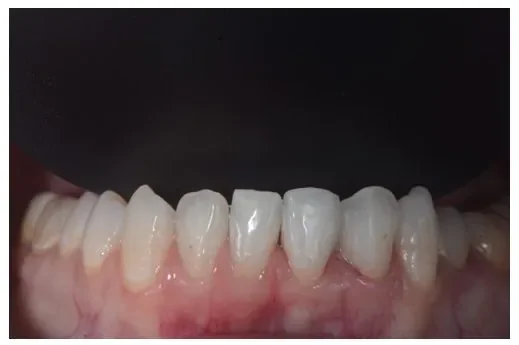

Before

After

ダイレクトボンディングの症例3

2週間、3回 / 66,000円リスク・副作用:経年的に歯間が開いてくる可能性及び接着低下によりレジン脱離、レジン周囲変色